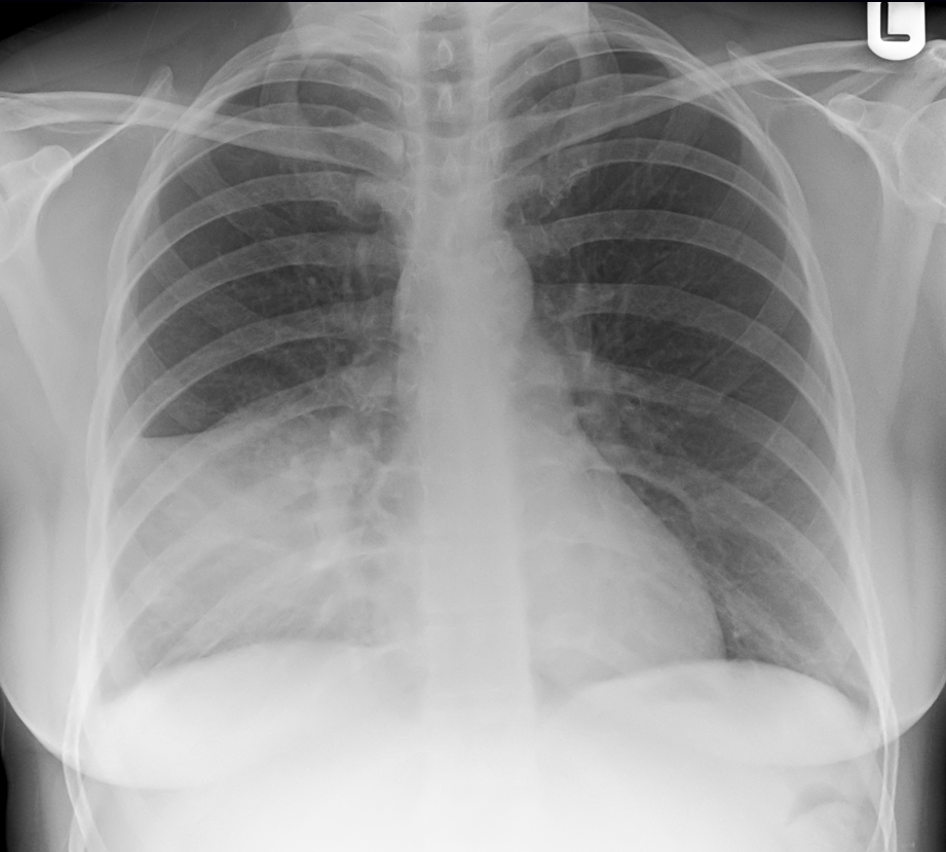

45

What is this ?

Right lower lobe pneumonia Ccant see right hemi diaphram and heart border with diaphragm Loss of right hemidiaphragm silhouette = right lower lobe involvement Right heart border visible = not primarily right middle lobe More consistent with pneumonia than congestion